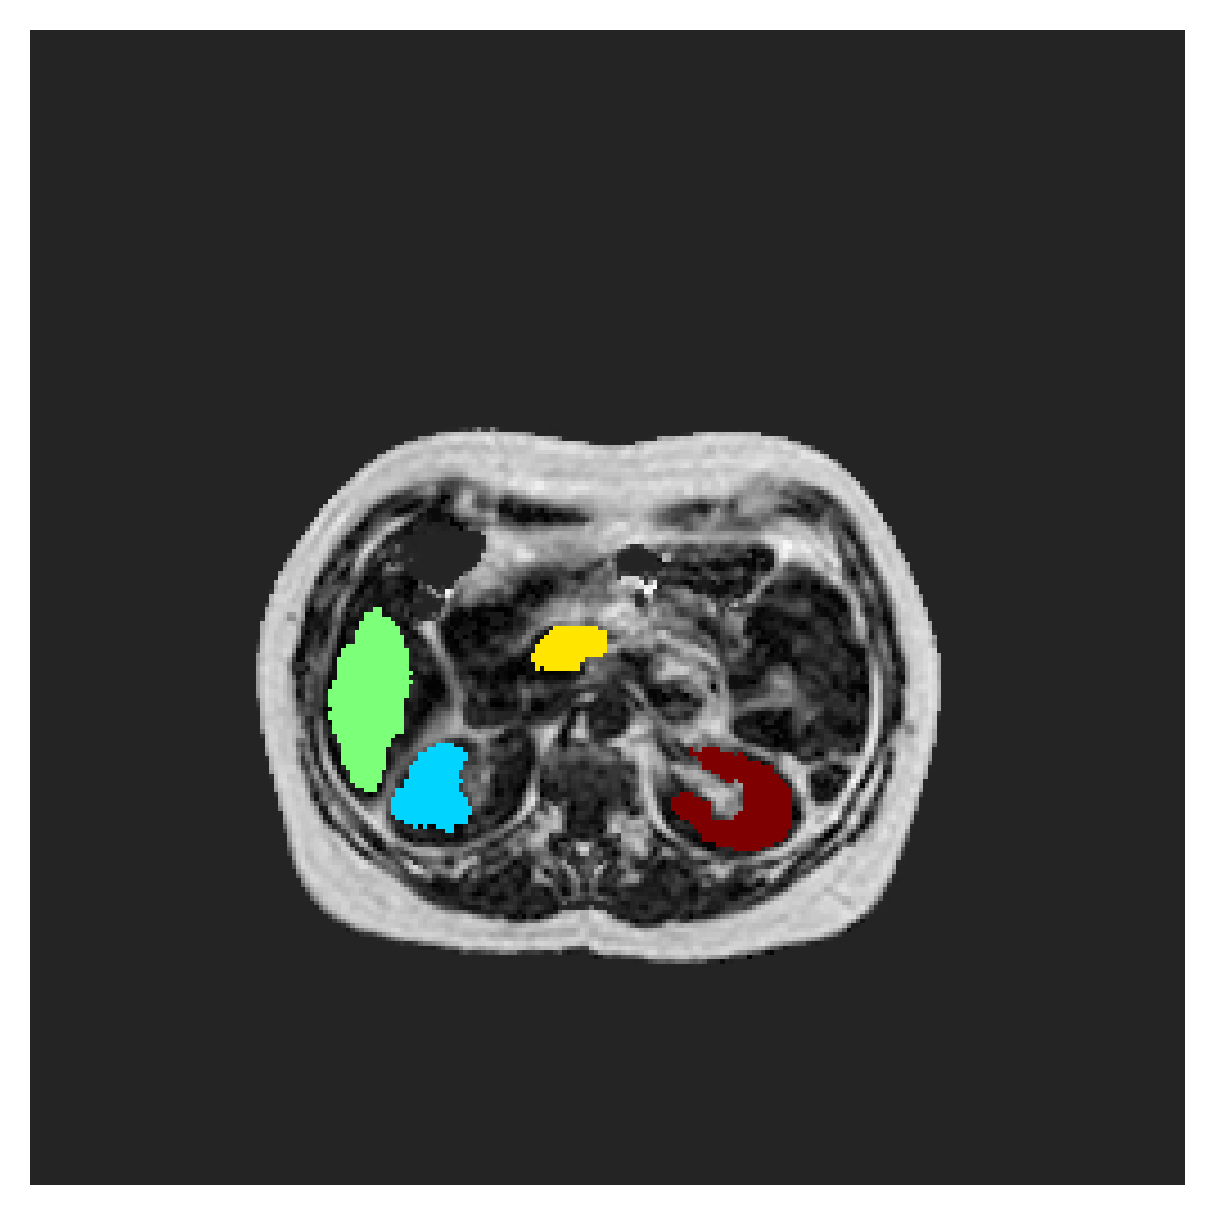

We normalize the volumes and resize the slices to pixels. As the official dataset comes with full annotations, we create a synthetic point ground truth. This is done by first randomly choosing the centers of the point annotations within the class masks, followed by filling an ellipse with axes lengths of and (in pixels) around each center. The intersections of these elliptic discs with the underlying full annotations are then used as our point ground truth. See Figure 2 for an example of the created weak annotation mask. The point annotations are created for every slice, one for each foreground object present in the slice.

POEM

The Prospective investigation of Obesity, ENergy production and Metabolism (POEM) is a local (not currently publicly available; PI: L. Lind, see [22] for details) cohort of whole-body fat/water separated MR images. Full annotations of the liver, kidneys, bladder, pancreas and spleen are available for 50 subjects, providing a challenging segmentation dataset with heavily imbalanced classes of varying shapes. The resolution of the data is anisotropic, with reconstructed voxel size of in left-right, anterior-posterior and foot-head directions, respectively. For additional technical details regarding the acquisition and specifications of the images see [22].

The images contain two channels, one for water and one for fat content. For training, we normalize the volumes (per channel) and use 2D slices in the coronal plane, sized . The weak annotations are created synthetically, following the same procedure as described for the ACDC dataset.

In Figure 6 we provide qualitative results on a number of randomly chosen test set slices. Upon visual inspection, we can observe that training with the intensity-aware distances (particularly with and ) follows the image gradients better and is better at recovering the underlying shape than the Euclidean version. The CRF-loss seems to recover the shape of the myocardium and left ventricle to some extent, but fails entirely on the right ventricle.

In Table 3, the average DSC and HD95 results are shown (both using 2D and 3D distance maps) for the task of abdominal organ segmentation in POEM data (for boxplots see figures 8 and 9). We see that training with and (with distances calculated on 2D slices) performs comparably, while using and produces lower scores in both DSC and HD95 metric. On this dataset, the CRF-loss is able to compete with the boundary loss-based training strategies, even outperforming them on most classes. Most notably, all models trained with boundary loss appear to have a hard time segmenting the liver. We hypothesize this may be due to extremely severe class imbalance, as the liver covers a very large area compared to the rest of the classes. It is thus also more strongly affected by undersegmentations.

5.2.1 Qualitative comparison

In Figure 11 and 12 we show the same random slices in cases of calculating the boundary loss on 2D- and 3D-based distances, respectively. Comparing the two figures again indicates that the intensity-aware distances offer most improvement when calculated in 3D over 2D. The exception here is the MBD, which seems to even slightly degrade for most classes.